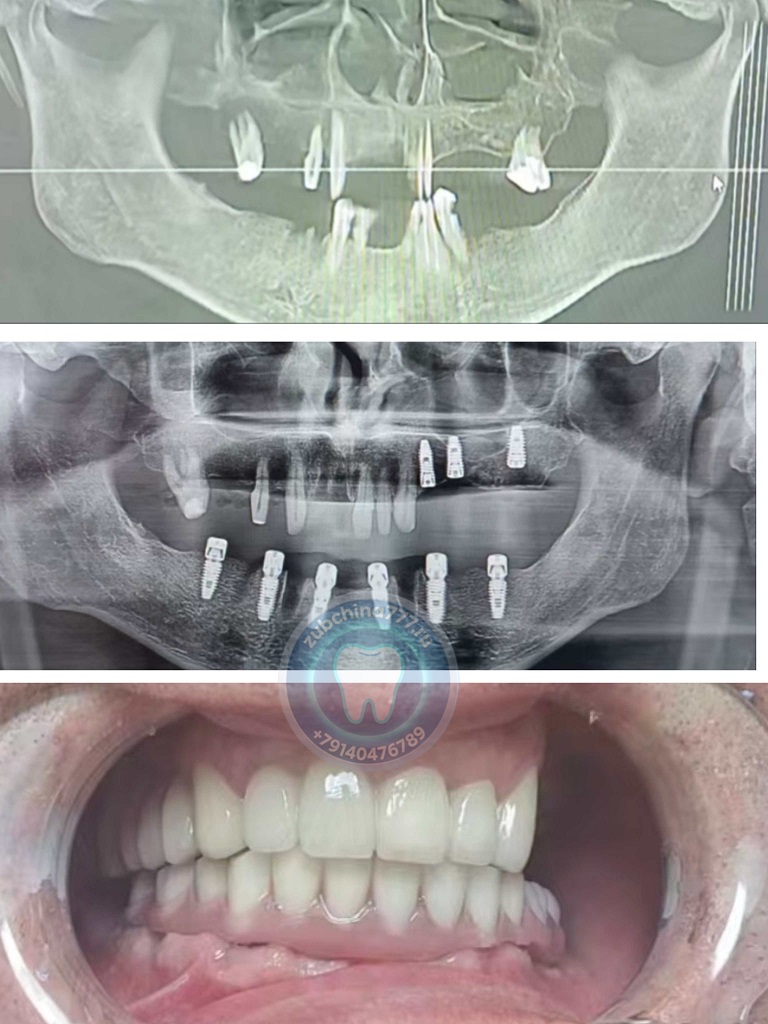

Фотографии пациентов ДО и ПОСЛЕ лечения и протезирования зубов в Хэйхэ